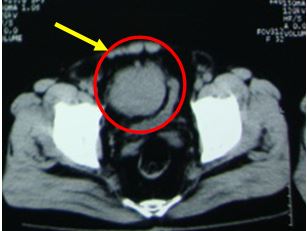

+ Bệnh nhân được tiến hành chụp cắt lớp vi tính ổ bụng để đánh giá cho thấy hình ảnh khối giảm tỷ trọng kích thước 70x90x100 mm, ranh giới rõ, bờ thùy múi, ngấm thuốc cản quang sau tiêm, trung tâm có vùng hoại tử không ngấm thuốc, khối u đè đẩy bàng quang ra sau và sang trái

Kết luận: Khối u vùng tiểu khung theo dõi lymphoma

Hình 2. Hình ảnh chụp cắt lớp vi tính ổ bụng: Khối u vùng hạ vị đè một phần vào bàng quang, đẩy bàng quang ra sau và sang trái